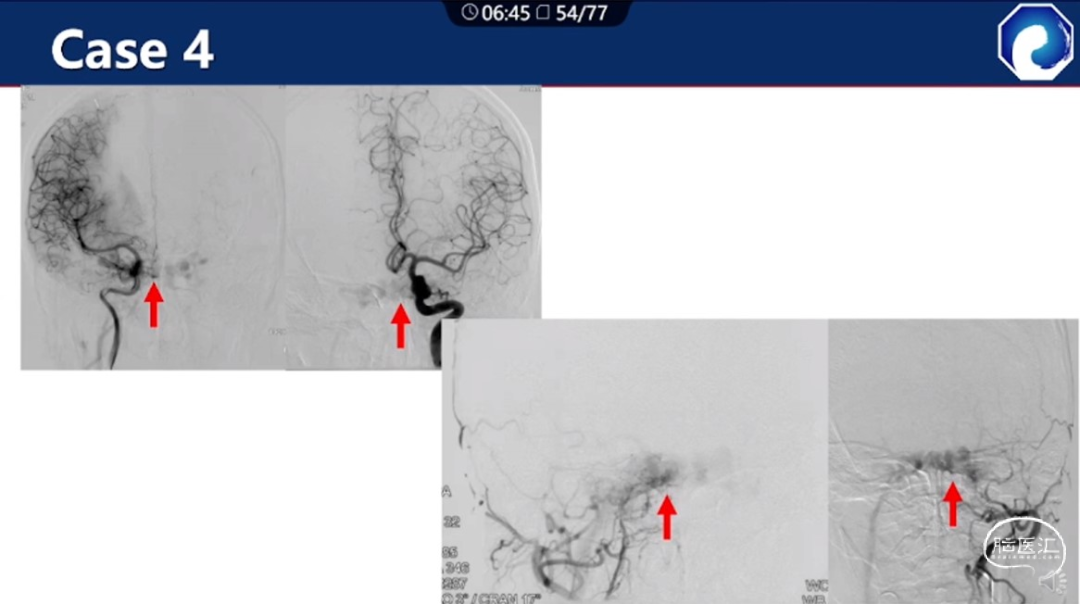

痿口静脉端的识别至关重要。

痿口静脉端精准完全闭塞是DAVF治愈的关键。

靶向性栓塞可以减少海绵窦分隔的过渡栓塞,有利于减少颅神经并发症,恢复海绵窦的正常引流功能。